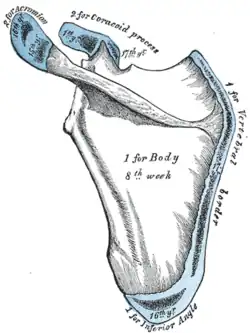

Os acromiale

The acromion has four ossification centers called (from tip to base) pre-acromion, meso-acromion, meta-acromion, and basi-acromion. In most cases, the first three fuse at 15–18 years, whereas the base part fuses to the scapular spine at 12 years. However, in between 1% and 15% of cases, this osseous union fails and the acromion remains separate as an accessory bone. This condition is referred to as os acromiale, but rarely causes pain. Earlier estimates of its prevalence were as low as 1.4%, and this higher estimate was made by Sammarco in the year 2000, based on radiographic and anatomical studies.[6][7]

Four types of os acromiale can be distinguished:[8]

- A non-union between the meso- and meta-acromia, the most common or typical os acromiale

- A non-union between the pre- and meso-acromia

- A non-union between the pre- and meso-acromia; and between the meso- and meta-acromia, atypical

- A non-union between the pre- and meso-acromia; between the pre- and meso-acromia; and between the meta- and basi-acromia

Plan of ossification of the scapula. Posterior side. Acromion visible at upper left, in blue.

Plan of ossification of the scapula. Posterior side. Acromion visible at upper left, in blue. -